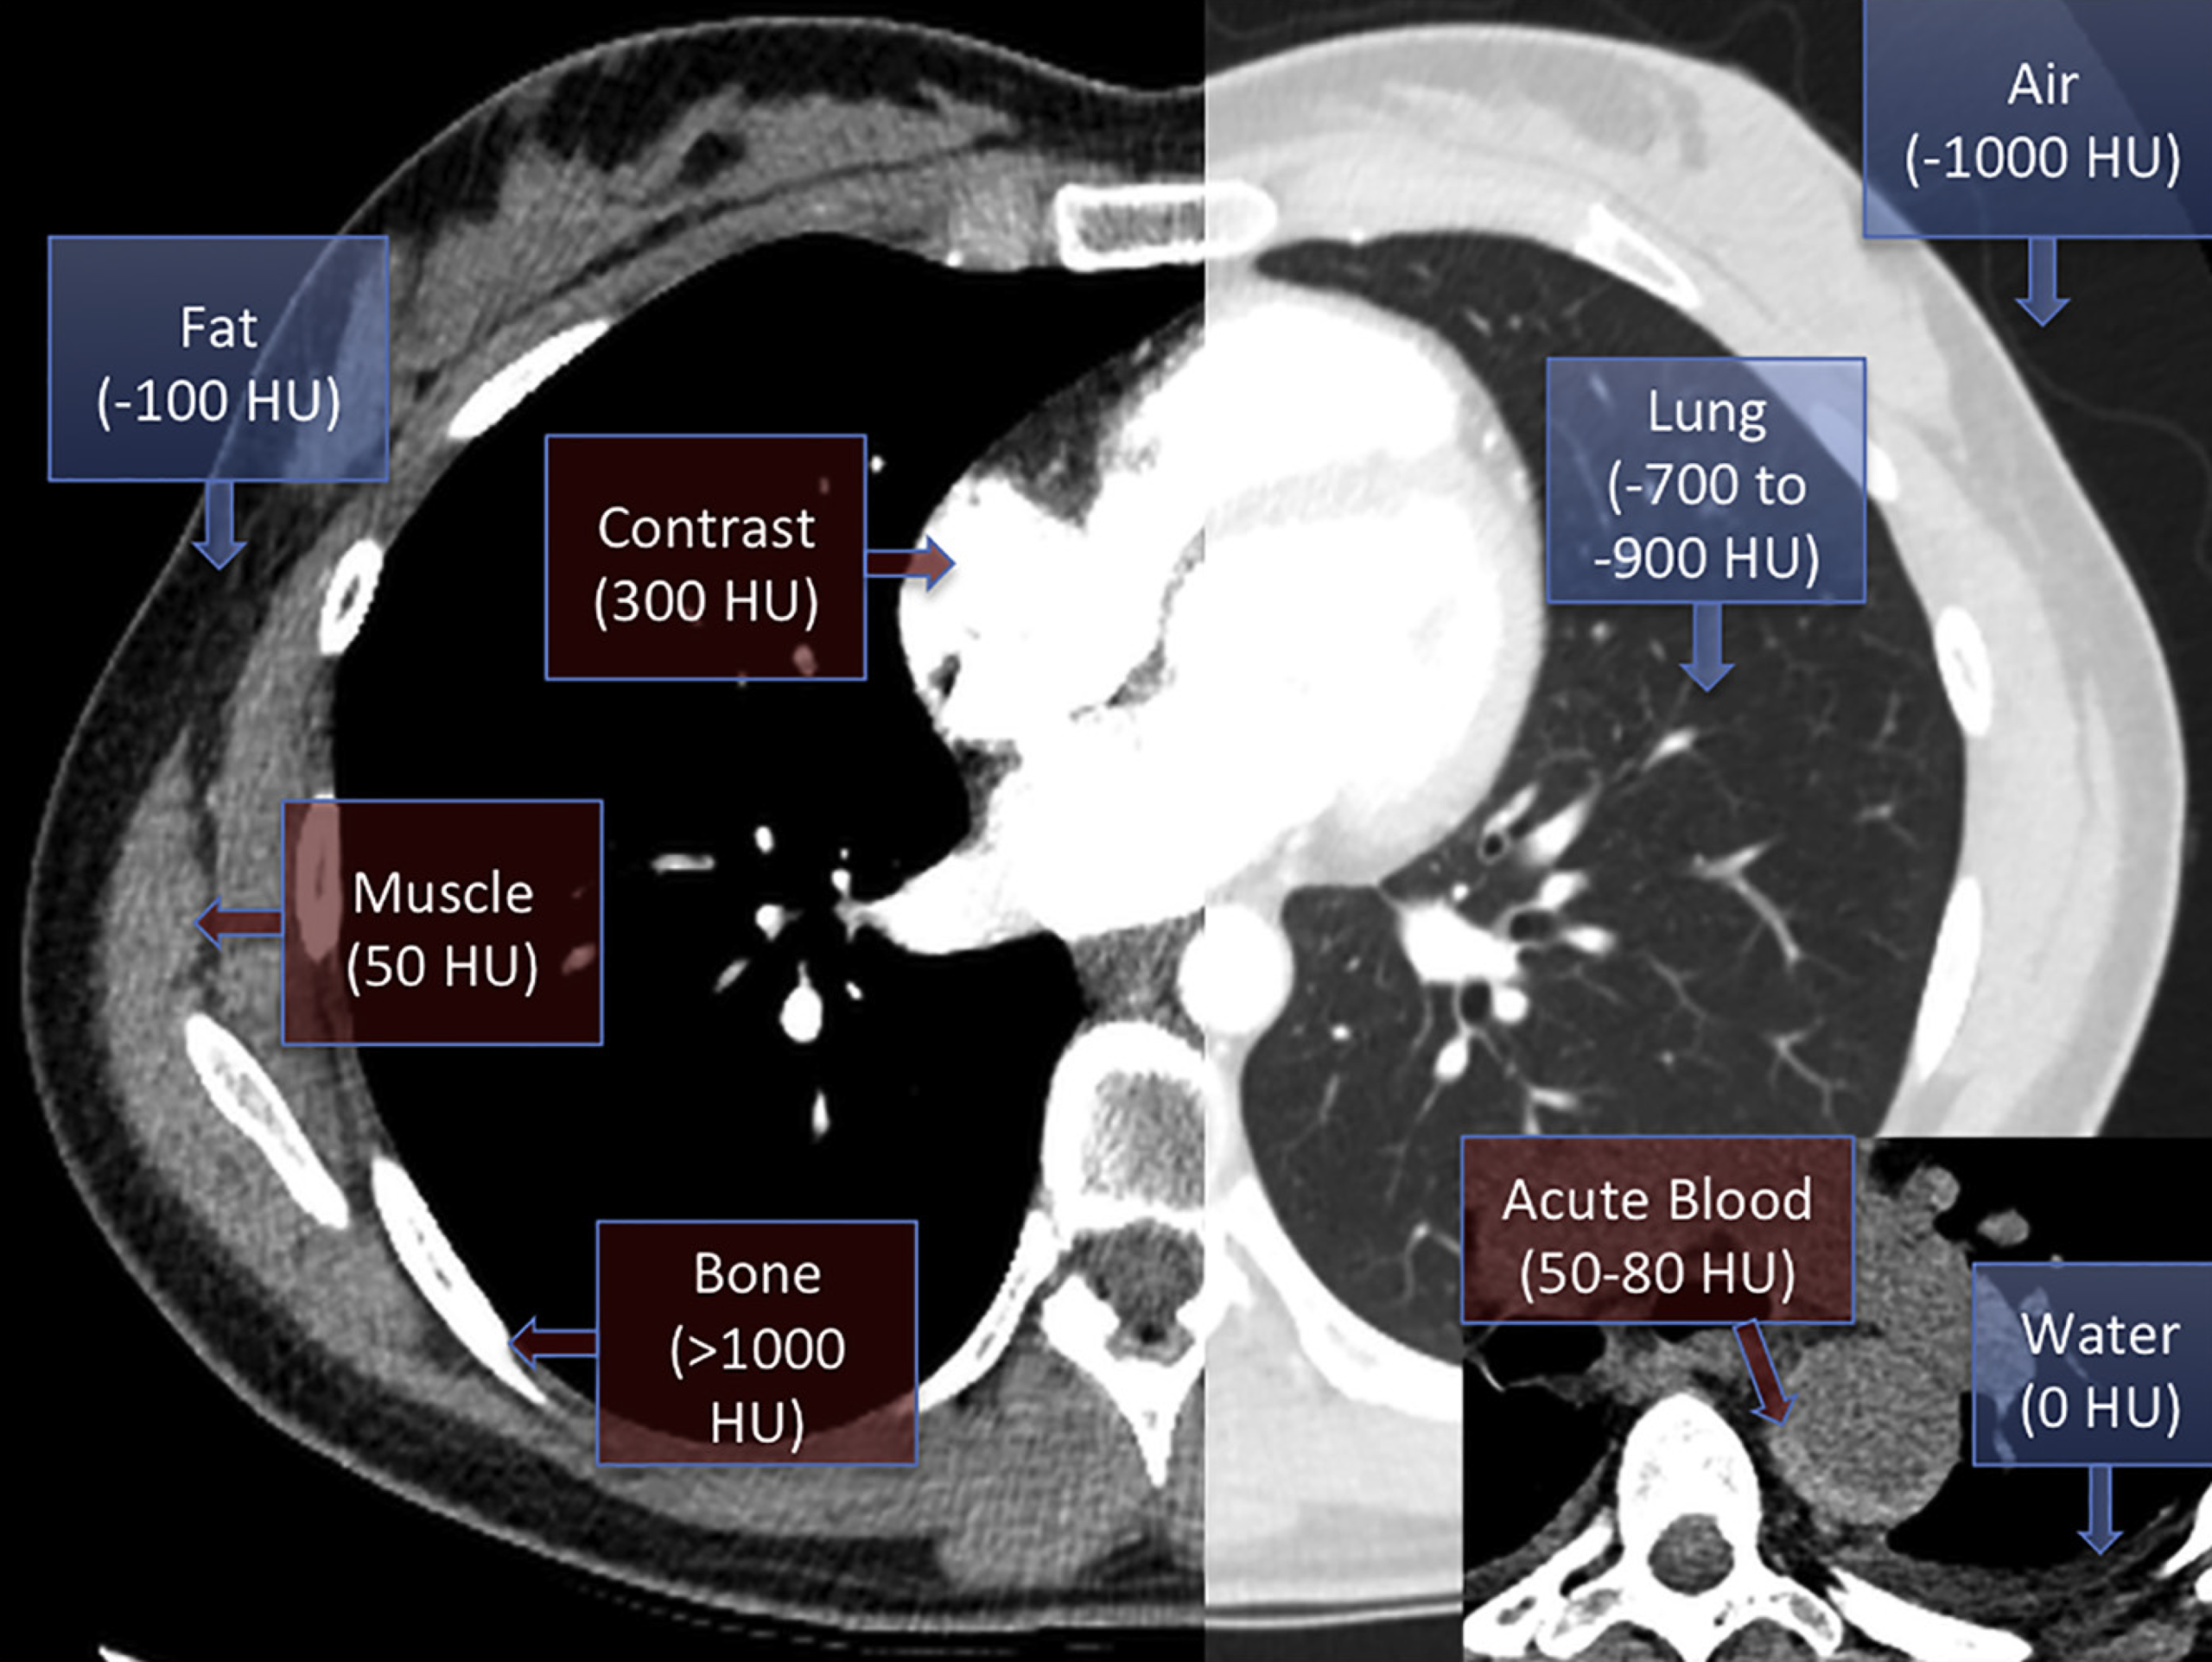

- A chest CT scan is highly sensitive for a pericardial effusion *.

- A CT scan may reveal the presence of posterior loculated effusion, clot, or abscess, which may not be visible via transthoracic echo.

- CT also provides valuable information about the possible nature of pericardial effusions based on the attenuation measurements of the collection *.

- Pericardial fluid with relatively low attenuation values close to that of water likely represents a simple serous effusion from underlying heart failure or nonhemorrhagic carcinomatous involvement.

- An attenuation value greater than that of water suggests hemopericardium, malignancy, purulent exudates, or myxedematous effusion associated with hypothyroidism.

🔎 Epicardial fat vs. pericardial effusion.

- In CT, the density (HU) of epicardial fat vs pericardial effusion is shown below. In echo, see here 🎥.